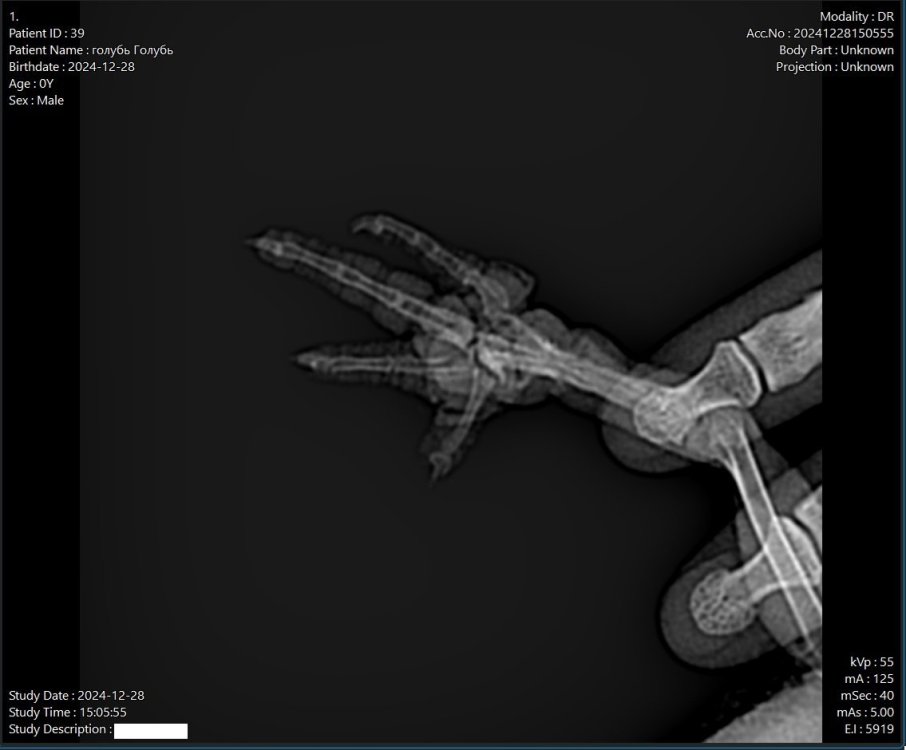

28 12.2024г. на балкон прилетел хромающий голубь. Вокруг была обернута леска и лапа опухшая, покрытая коркой. Поймали, свозили в вет.клинику, там удалили леску полностью, дезинфицировали хлоргексидином. На следующий день сделали рентген лапы. Рентген прилагаю. Сделали анализы. Прописали лечение:

Поясните пожалуйста, что означает рентгеновские снимки. Там сухожилия, кровеносная система, нервы повреждены? Отчего пропала у птицы возможность сгибать пальцы.   Там изначально леска была намотана и обморожение, все в корках. Они сошли, кроме еще кончика среднего пальца. Насколько все по фото или рентгену восстановиться может?

Поясните пожалуйста, что означает рентгеновские снимки

нужно чтобы @Zosia рентген посмотрела

Буду рад, если Зося посмотрит рентген, я выше в первом сообщении прикладывал. Попробовали сегодня пальцы на лапе позаминать, в виде массажа. Пальцы не гнутся книзу, как на второй лапе. Только ровно стоят, кроме мизинца который чуть загнут и большого пальца, (его положение мне вообще непонятно, попробовали его отогнуть чуть назад в уровень здорового большого пальца как на второй лапе, не удалось разогнуть так).